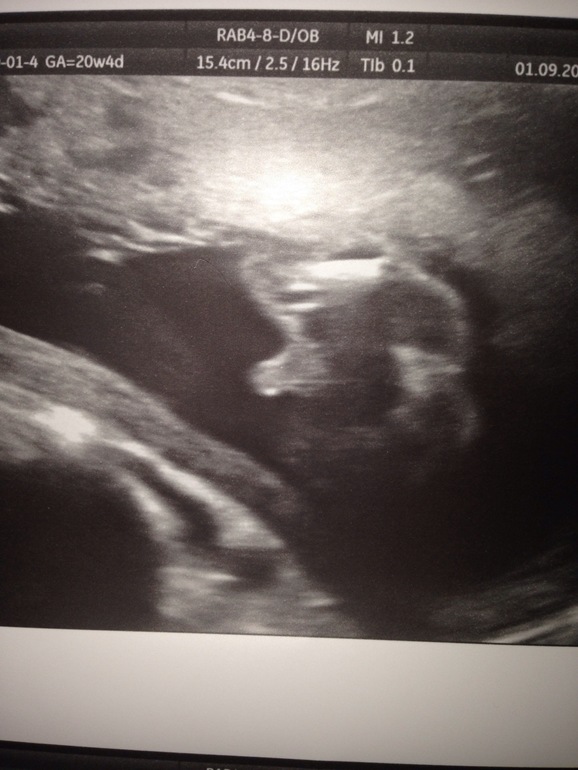

УЗИ в 20 неделек и ..... ТА-ДААА-М - у нас мальчик

УЗИ, КТГ, доплерНе знаю почему, но именно сегодня мне в голову ударило, что прям надо сходить на УЗИ, именно сегодня. Направление аж на 15 сентября выдали. Любопытство просто раздирало, в 12 нед нам не сказали, кто у нас будет. И вот долгожданный момент - мальчик!!! Папочка наш очень обрадовался, и единолично решил назвать малыша в честь дедушки. А дедушку у нас звать Магомед (в Дагестане это имя весьма распространено). И вот ситуация: я за Эльдара, он за Магомеда. В общем, мне хотелось бы дать более интернациональное имя.... Как переубедить нашего папочку? К слову сказать, я тут пошутила недавно. Второго назовем в честь моего папы. Вот и получится Магомед Аликович и Алексей Аликович!